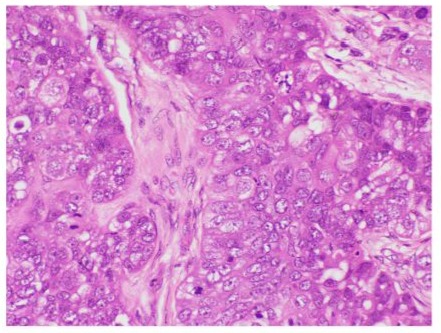

Figure 6: Microphotograph demonstrating lobules with high grade sebaceous gland cells (Hematoxylin & Eosin at magnification X40).